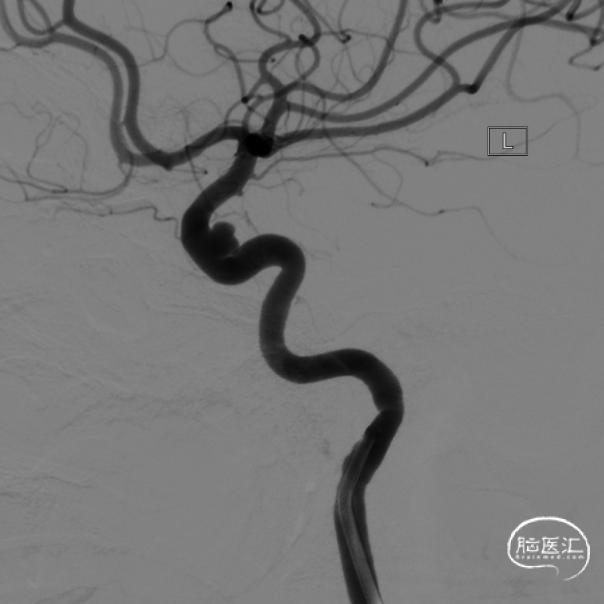

选择一枚3D弹簧圈进行成篮,紧接着选用多枚加奇生物的Jasper®颅内可电解脱弹簧圈进行后续填塞, 4mm×8cm 1枚,4mm×6cm 1枚,3mm×8cm 1枚,2mm×4cm 2枚致密填塞动脉瘤。撤出栓塞微导管,完全释放支架。工作角度造影见支架完全打开,动脉瘤无显影。

行标准正侧位造影发现动脉瘤无显影,载瘤动脉及远端分支血管通畅。股动脉造影后,撤出导引导管,拔除鞘管,Angio-Seal 1枚缝合血管穿刺点。病人术后麻醉清醒安返监护病房。